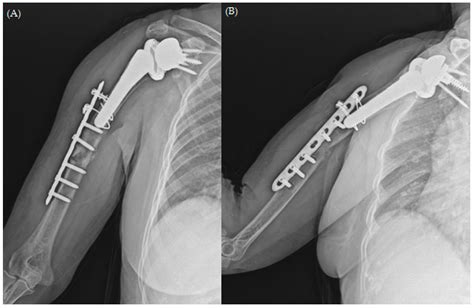

Premium Vector | Clavicle collar bone scapula shoulder blade humerus ...